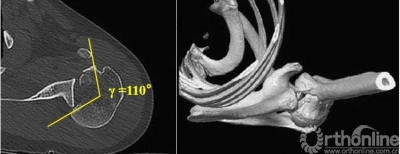

2.肩关节CT

确定肩关节后脱位。

了解反Hill-sachs损伤和程度。

观察肱骨近端主要骨折线和次要骨折线及形态。

五、反Hill-Sachs 损伤对肩关节稳定性的影响

1.反Hill-Sachs损伤范围对肩关节后方稳定性具有决定性的影响。

2.常规的影像学测量方法不能准确反映损伤范围。

3.反Hill-Sachs损伤合并反Bankart损伤被Moroder命名为“双极损伤”。

4.δ角是发生肱骨头后脱位所需的肩关节内旋角度,在双极损伤中δ角减小,所以在双极损伤中,即使较轻的反Hill-Sachs损伤也需要修复。